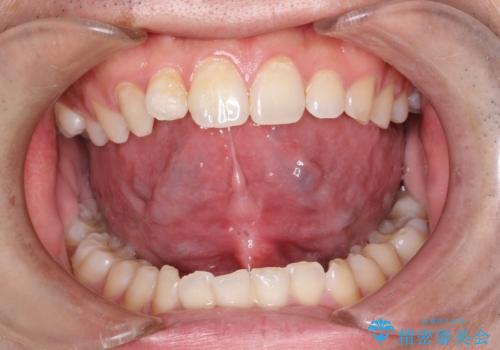

[舌小帯の形成術] 舌の動きが悪い 滑舌を改善したい!

![[舌小帯の形成術] 舌の動きが悪い 滑舌を改善したい!の症例 治療後](https://seimitsushinbi.jp/wp/wp-content/uploads/2025/06/3J7A9983-500x350.jpg?v=1750240491)